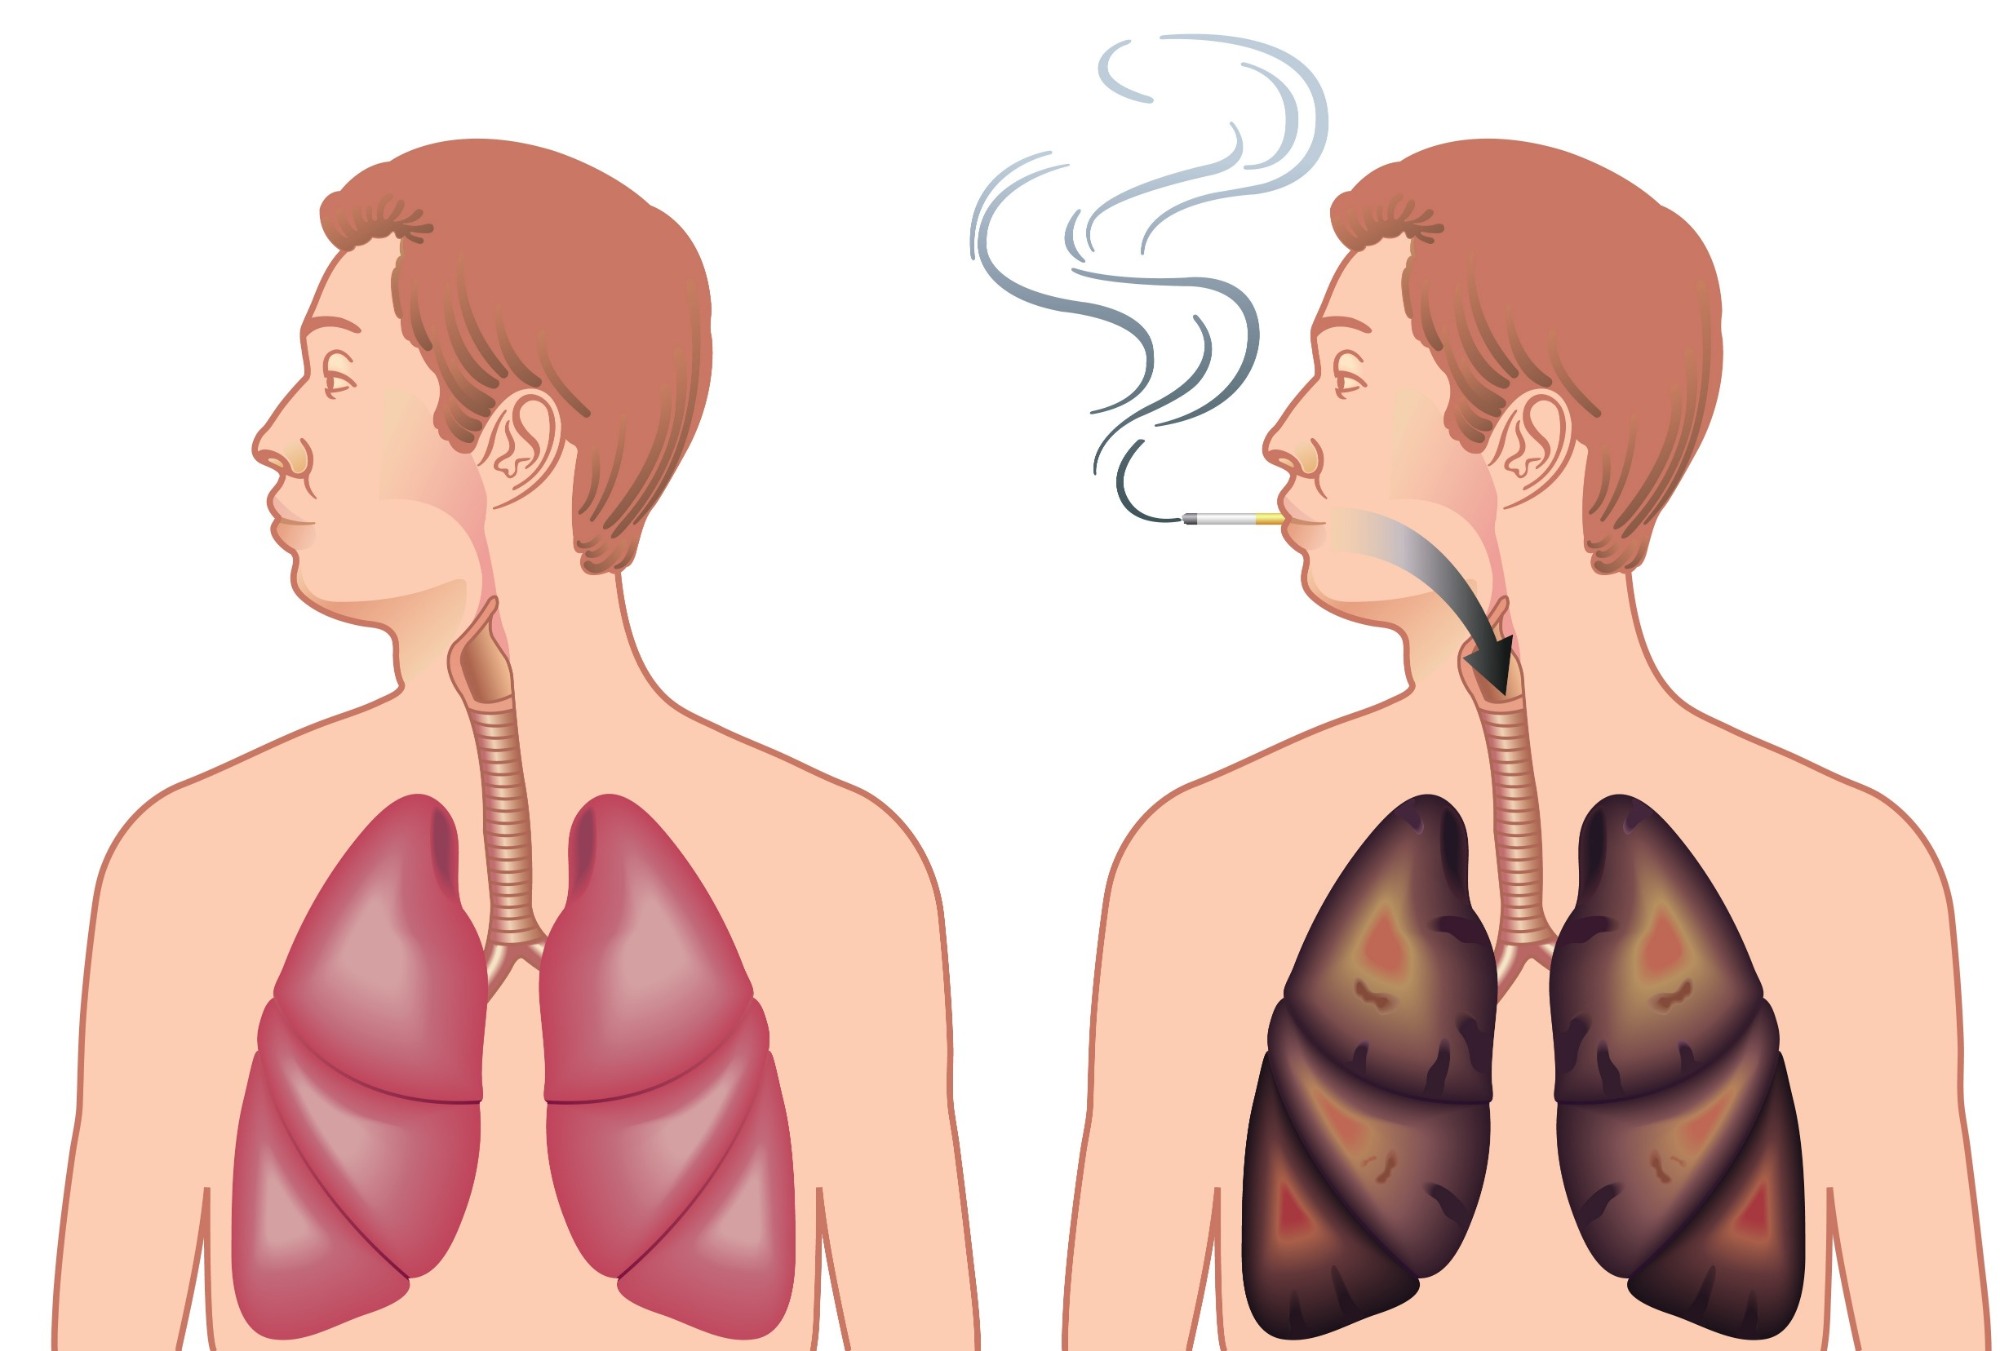

Hoe herstellen jouw longen zich wanneer je stopt met roken? Dokter.nl

Uitslag; klein vlekje op linkerlong. gedacht werd aan een longontsteking dus antibiotica gehad. Hij heeft echter geen klachten dus dat kwam voor ons uit de lucht vallen. Mij man is 31 jaar en heeft wel wat jaren gerookt maar sinds 5-6 jaar niet meer. Na een week antibiotoca een nieuwe foto gemaakt, en wat blijkt; niets veranderd op de foto.